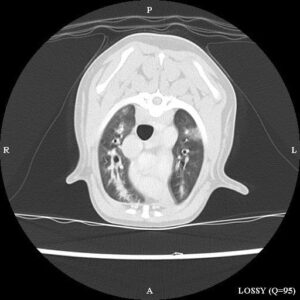

“A CT scan of the chest revealed severe and widespread thickening of the walls of the small airways, with complete obliteration of the airways in places.